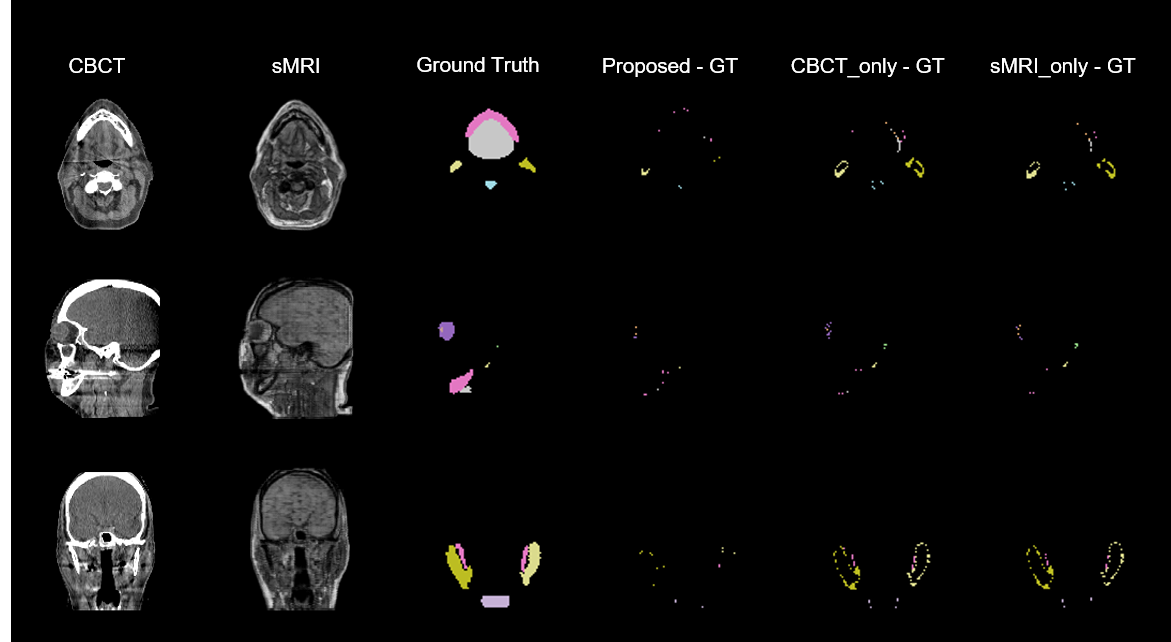

For comparison, we conducted all the experiments on both the proposed method (CBCT+sMRI), the approach using the same network (dual pyramid networks) excluding cycleGAN but only taking CBCT as inputs (two channels of CBCTs were used as inputs of the DPN without synthetic MRI), which we named as CBCT_only, and the method using dual pyramid networks but taking sMRI for the two channel inputs, which we named as sMRI_only approach. Figure 3 shows the results from one patient. Five different transverse slices are shown in five rows. The leftmost two columns are respectively CBCT and sMRI images, followed by the next four columns respectively showing the ground truth, the discrepancies of the proposed method predicted, CBCT_only predicted, sMRI_only predicted contours referring to the ground truth. Figure 4 shows the three orthogonal views (axial, sagittal, and coronal) of another case. The rows from left to right show the CBCT, sMRI, the ground truth, the differences between the ground truth and the predictions by our proposed, CBCT_only, sMRI_only methods respectively. Qualitatively investigating on the images in Figures 3 and 4, we can see, the predicted contours from our proposed method have less discrepancies with the ground truth than either CBCT_only or sMRI_only method, attribute to the strength of combining the complementary features extracted from CBCT and synthetic MRI images.

[Uncaptioned image]

Fig. 4. Three orthogonal views of one case. sMRI, synthetic MRI; Proposed – GT, the discrepancy between the proposed predicted contours and the ground truth; CBCT_only – GT, the difference between CBCT_only predicted contours and the ground truth; sMRI_only – GT, the discrepancy between sMRI_only prediction and the ground truth.